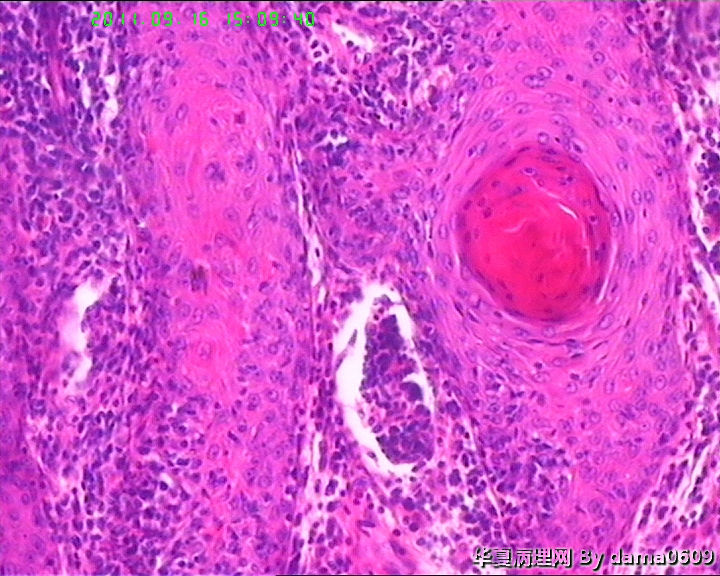

女,背部皮肤肿物,病史不详。送检梭皮组织一块,S:4.5x2.2cm,正中一圆形隆起,直径2.0cm,表面黄白色与周围界清,切面实性灰白色。

• 背部肿物,急请老师看看!!图1

图1